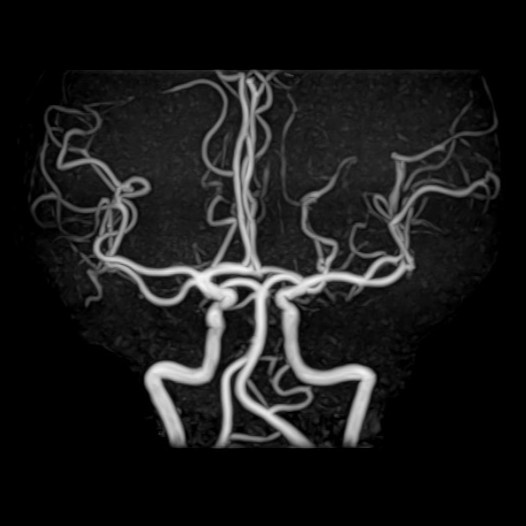

脳ドック

脳の健康診断も行っております。脳卒中や脳腫瘍、脳動脈瘤などの脳疾患は、発症する前の早期発見・予防が非常に重要です。 当院ではMRIを用いた「脳ドック」を実施し、無症状の段階での脳の異常をチェックすることが可能です。 詳しくは人間ドックのご案内(PDF)をご覧ください。